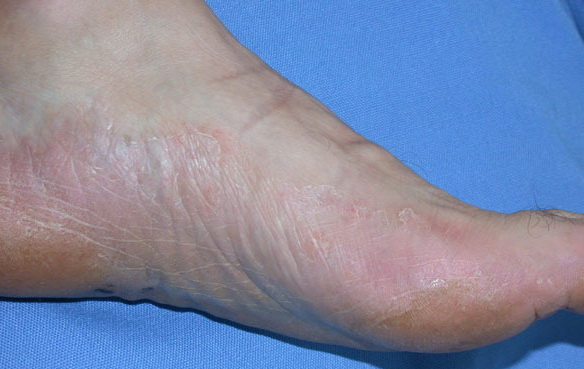

Chronic Hyperkeratotic Type.

Usually bilateral with patchy or diffuse scaling limited to the thick skin, soles, and the lateral and medial aspects of the feet, this is also known as “moccasin-type” tinea pedis. T. rubrum, the most common etiology, produces very few minute vesicles, leaving collarettes of scale less than 2 mm in diameter. Erythema is variable.

Unilateral tinea manuum commonly occurs in association with hyperkeratotic tinea pedis, resulting in the “two feet-one hand syndrome” . When tinea manus extend to the dorsum of a hand, it assumes the clinical pattern of tinea corporis . Oral antifungals are often required for treatment due to the high incidence of concomitant onychomycosis and relapse.